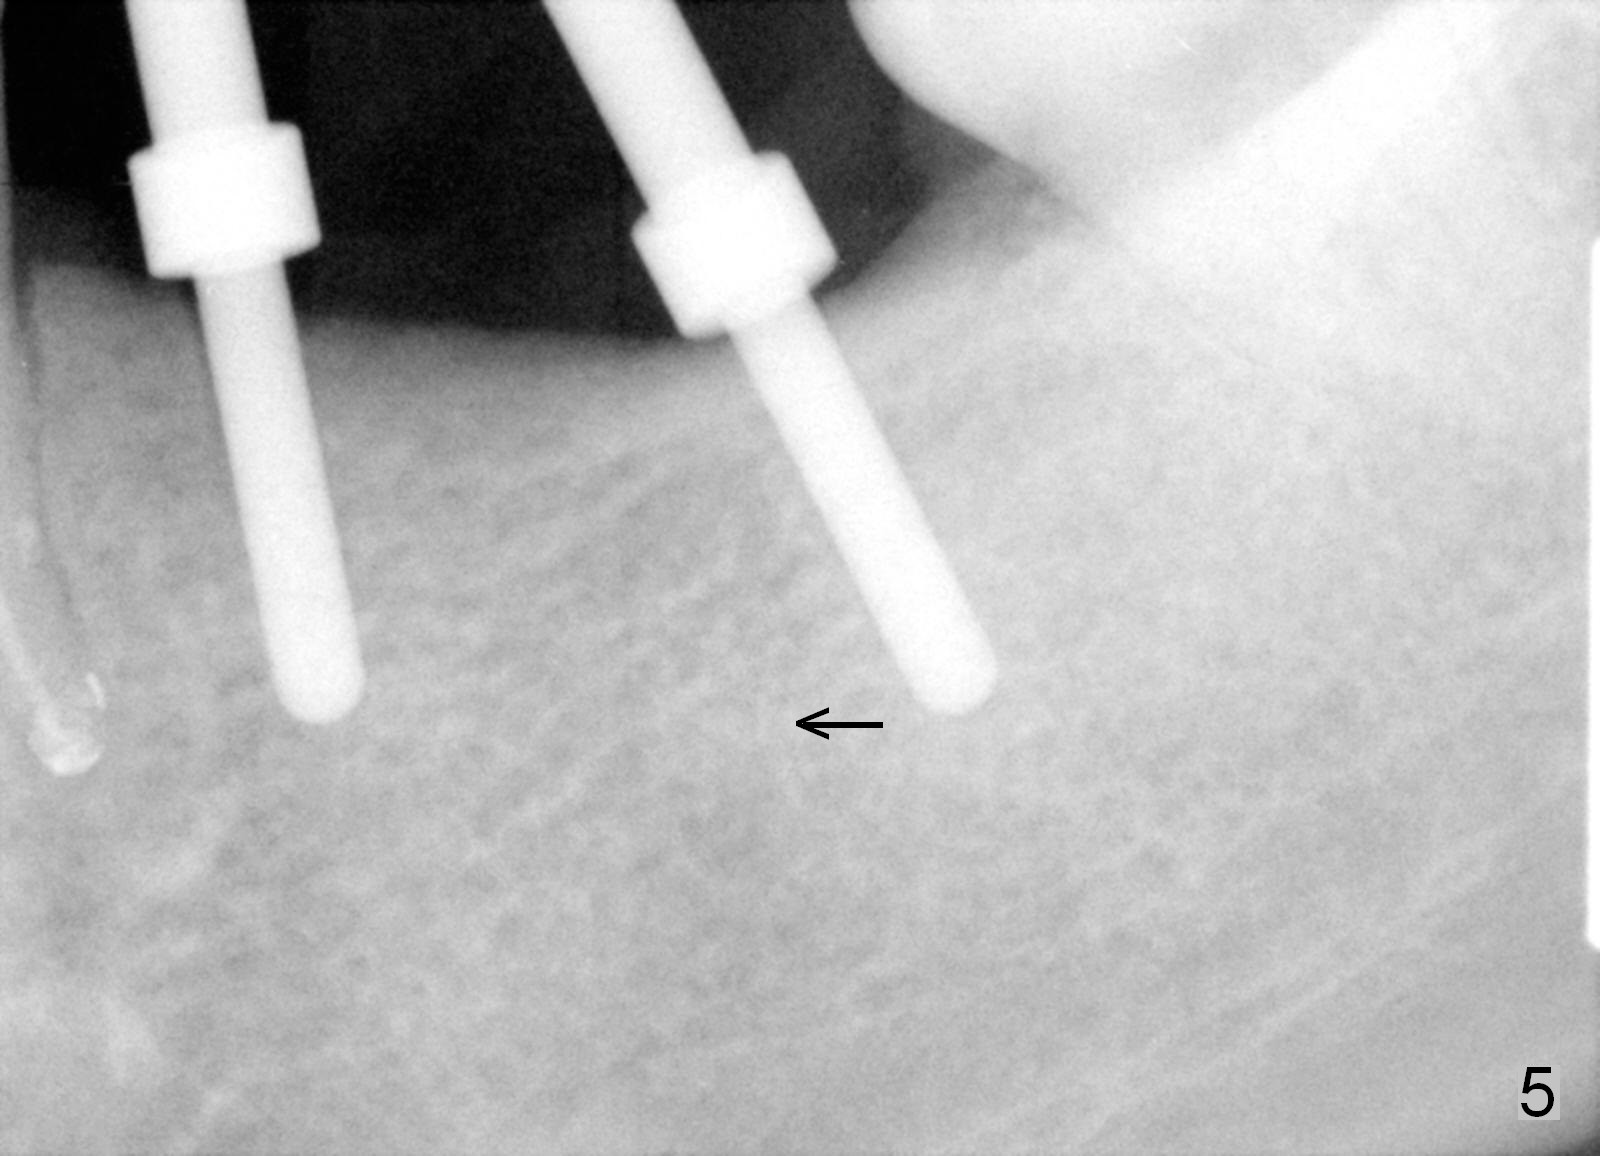

One year 2 months post root canal therapy at #20 (Fig.4), osteotomies are initiated at #18 and 19. The trajectory at #19 is subsequently corrected (Fig.5); that of #18 should be also corrected (arrow). The fact of the narrow ridge (Fig.6) is also ignored intraop. Without further adjustment, the osteotomies are enlarged (Fig.7) and the implants are placed (Fig.8: 4.5x14, 5x14 mm). As expected, the buccal coronal implant surface is exposed. The buccal plate is decorticated with placement of autogenous bone graft. Periodontal dressing is applied. Postop, the wound is infected with wound gapping. With irrigation, the wound finally heals.